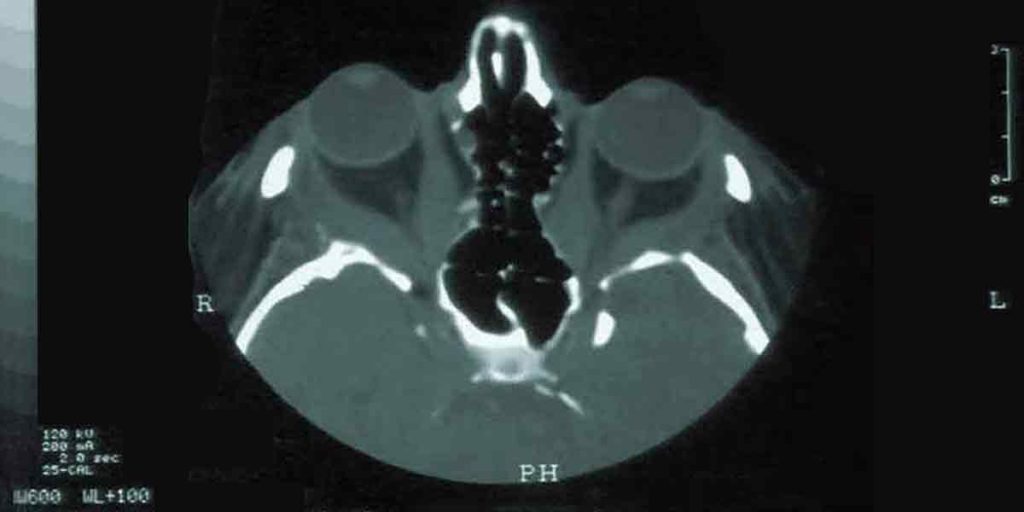

Because the orbit is surrounded by bone, there is little room for expansion. As the inflamed tissue enlarges, the eye is gradually pushed forward, a process called exophthalmos. The forward displacement can make eyelids retract and prevent complete closure of the eye, causing exposure, dryness, and irritation. In advanced cases, the optic nerve at the back of the orbit can be compressed, endangering vision and requiring urgent intervention.

Once the inflammatory phase has stabilized, orbital decompression surgery can restore the natural position of the eyes. During this operation, small sections of orbital bone and, when needed, excess orbital fat are removed to relieve pressure and create space within the orbit. The eye then settles backward into a more normal alignment, improving both function and appearance.